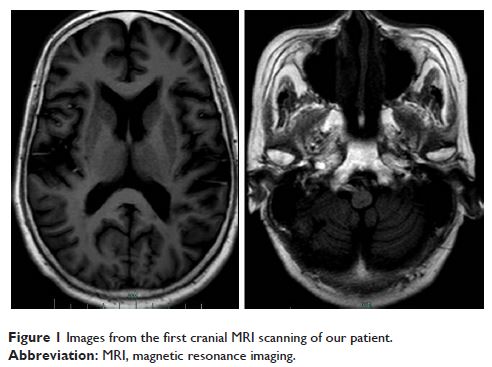

Case Report

- 作者:Jinfeng Duan, Chengming Lao, Jingkai Chen, Fen Pan, Chenlin Zhang, Weijuan Xu, Weihua Zhou, Jianbo Hu, Desheng Shang, Manli Huang, Yi Xu

- 期刊:Neuropsychiatric Disease and Treatment